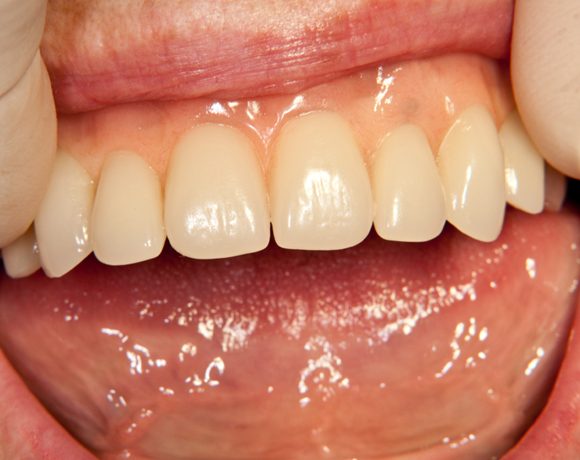

Der SFI-Bar® ist die innovative Steglösung für die abnehmbare Prothetik auf 2-6 Implantaten im Ober- und Unterkiefer.

1 . Immediate loading: Hohe Patientenakzeptanz und gute Osseointegration

+ Gesamte Behandlung in einer Sitzung

3. Chair- und Labside-Verarbeitung: Zeitsparende Herstellung

+ Wirtschaftliche Lösung

+ Hohe Zeitersparnis